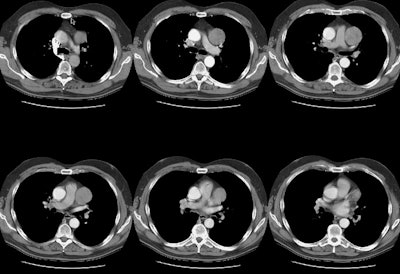

Benign Thymoma:

The patient shown in the CT scan below presented for evaluation of an abnormality detected on plain film as part of a routine physical. The patient had no neurologic symptoms. The CT demonstrates a slightly heterogeneous mass in the aorto-pulmonary window. No other lesions or adenopathy was identified. The patient was suspected to have a mediastinal lymphoma, but at histologic examination, the mass was found to be a benign thymoma.